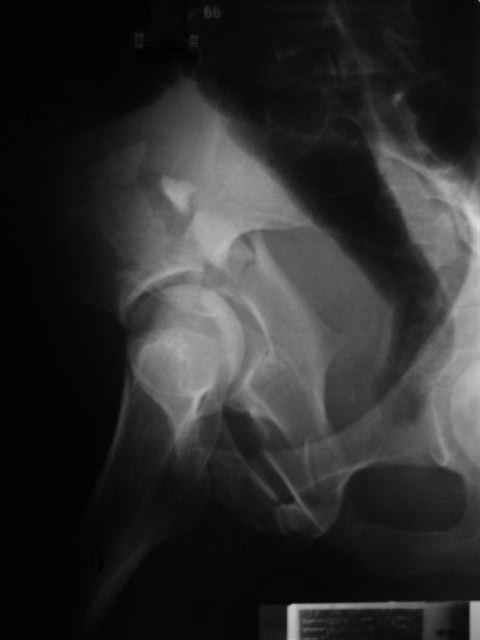

Уважаемые коллеги,43 летний мужчина, попав в автоаварию 13.10.2004, получил оскольчатый перелом обеих колонн левой вертлужной впадины.

На рентгенограммах - высокий двухколонный перелом вертлужной впадины с нарушением конгруэнтности, имеется обратная клиновидность суставной щели.